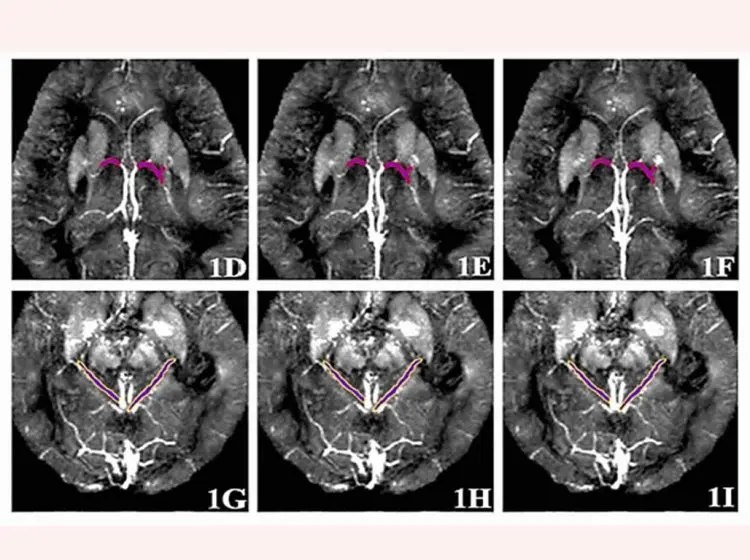

Пермский Политех достигает успехов в ранней диагностике Альцгеймера с помощью МРТ вен мозга Ученые Пермского Политеха придумали супер-пупер метод диагностики Альцгеймера на ранней стадии! Они используют МРТ и волшебные алгоритмы, которые с точностью до 89% определяют болезнь по состоянию вен в мозге. Круто, правда? Главное – это помощь врачам, а не замена их профессионализма. 📢 Читать далее: t-nw.ru 📸 Фото: scientificrussia.ru 🔔 Подписывайтесь на нас: t_nw_press